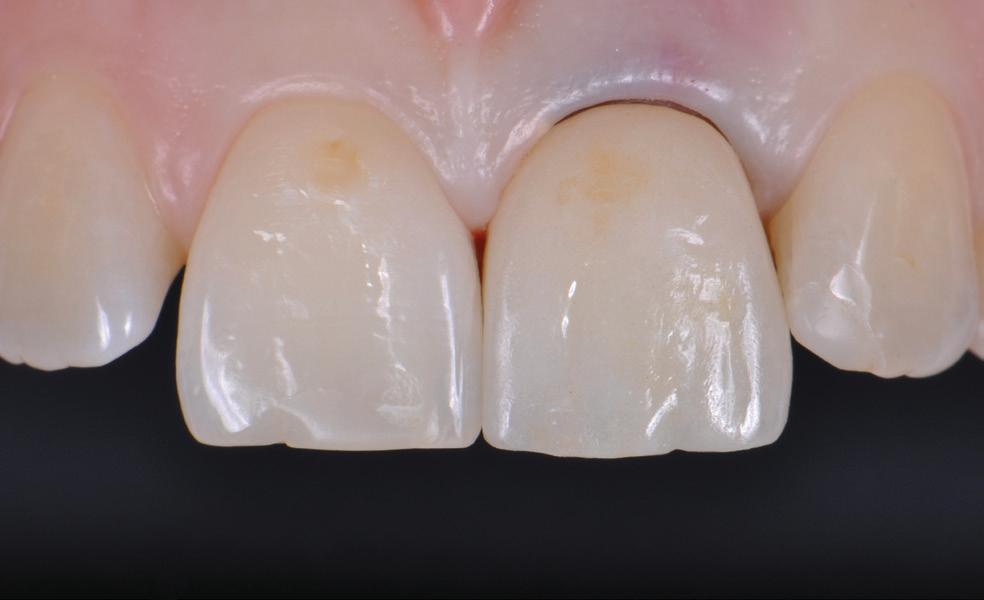

Many of the “valuation” enquiries I received were in fact requests for help with dental business problems in which case the dentist’s hidden agendas were identified and dealt with but valuation not proceeded with. 33 years of examining dental financials, including benchmarking dental practice efficiency, doing tax planning for dentists, helping dentists negotiate practice buy and sell agreements or sensitive dental associateships, gave me a rewarding insight into the Australian dental profession. I was fortunate to enjoy dental client relationships Australia-wide and to observe the differences in practice of financially very successful dentists and some who have struggled.

Knowing your own practice.